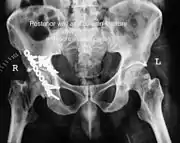

| Acetabular fracture as seen on plain X-ray |